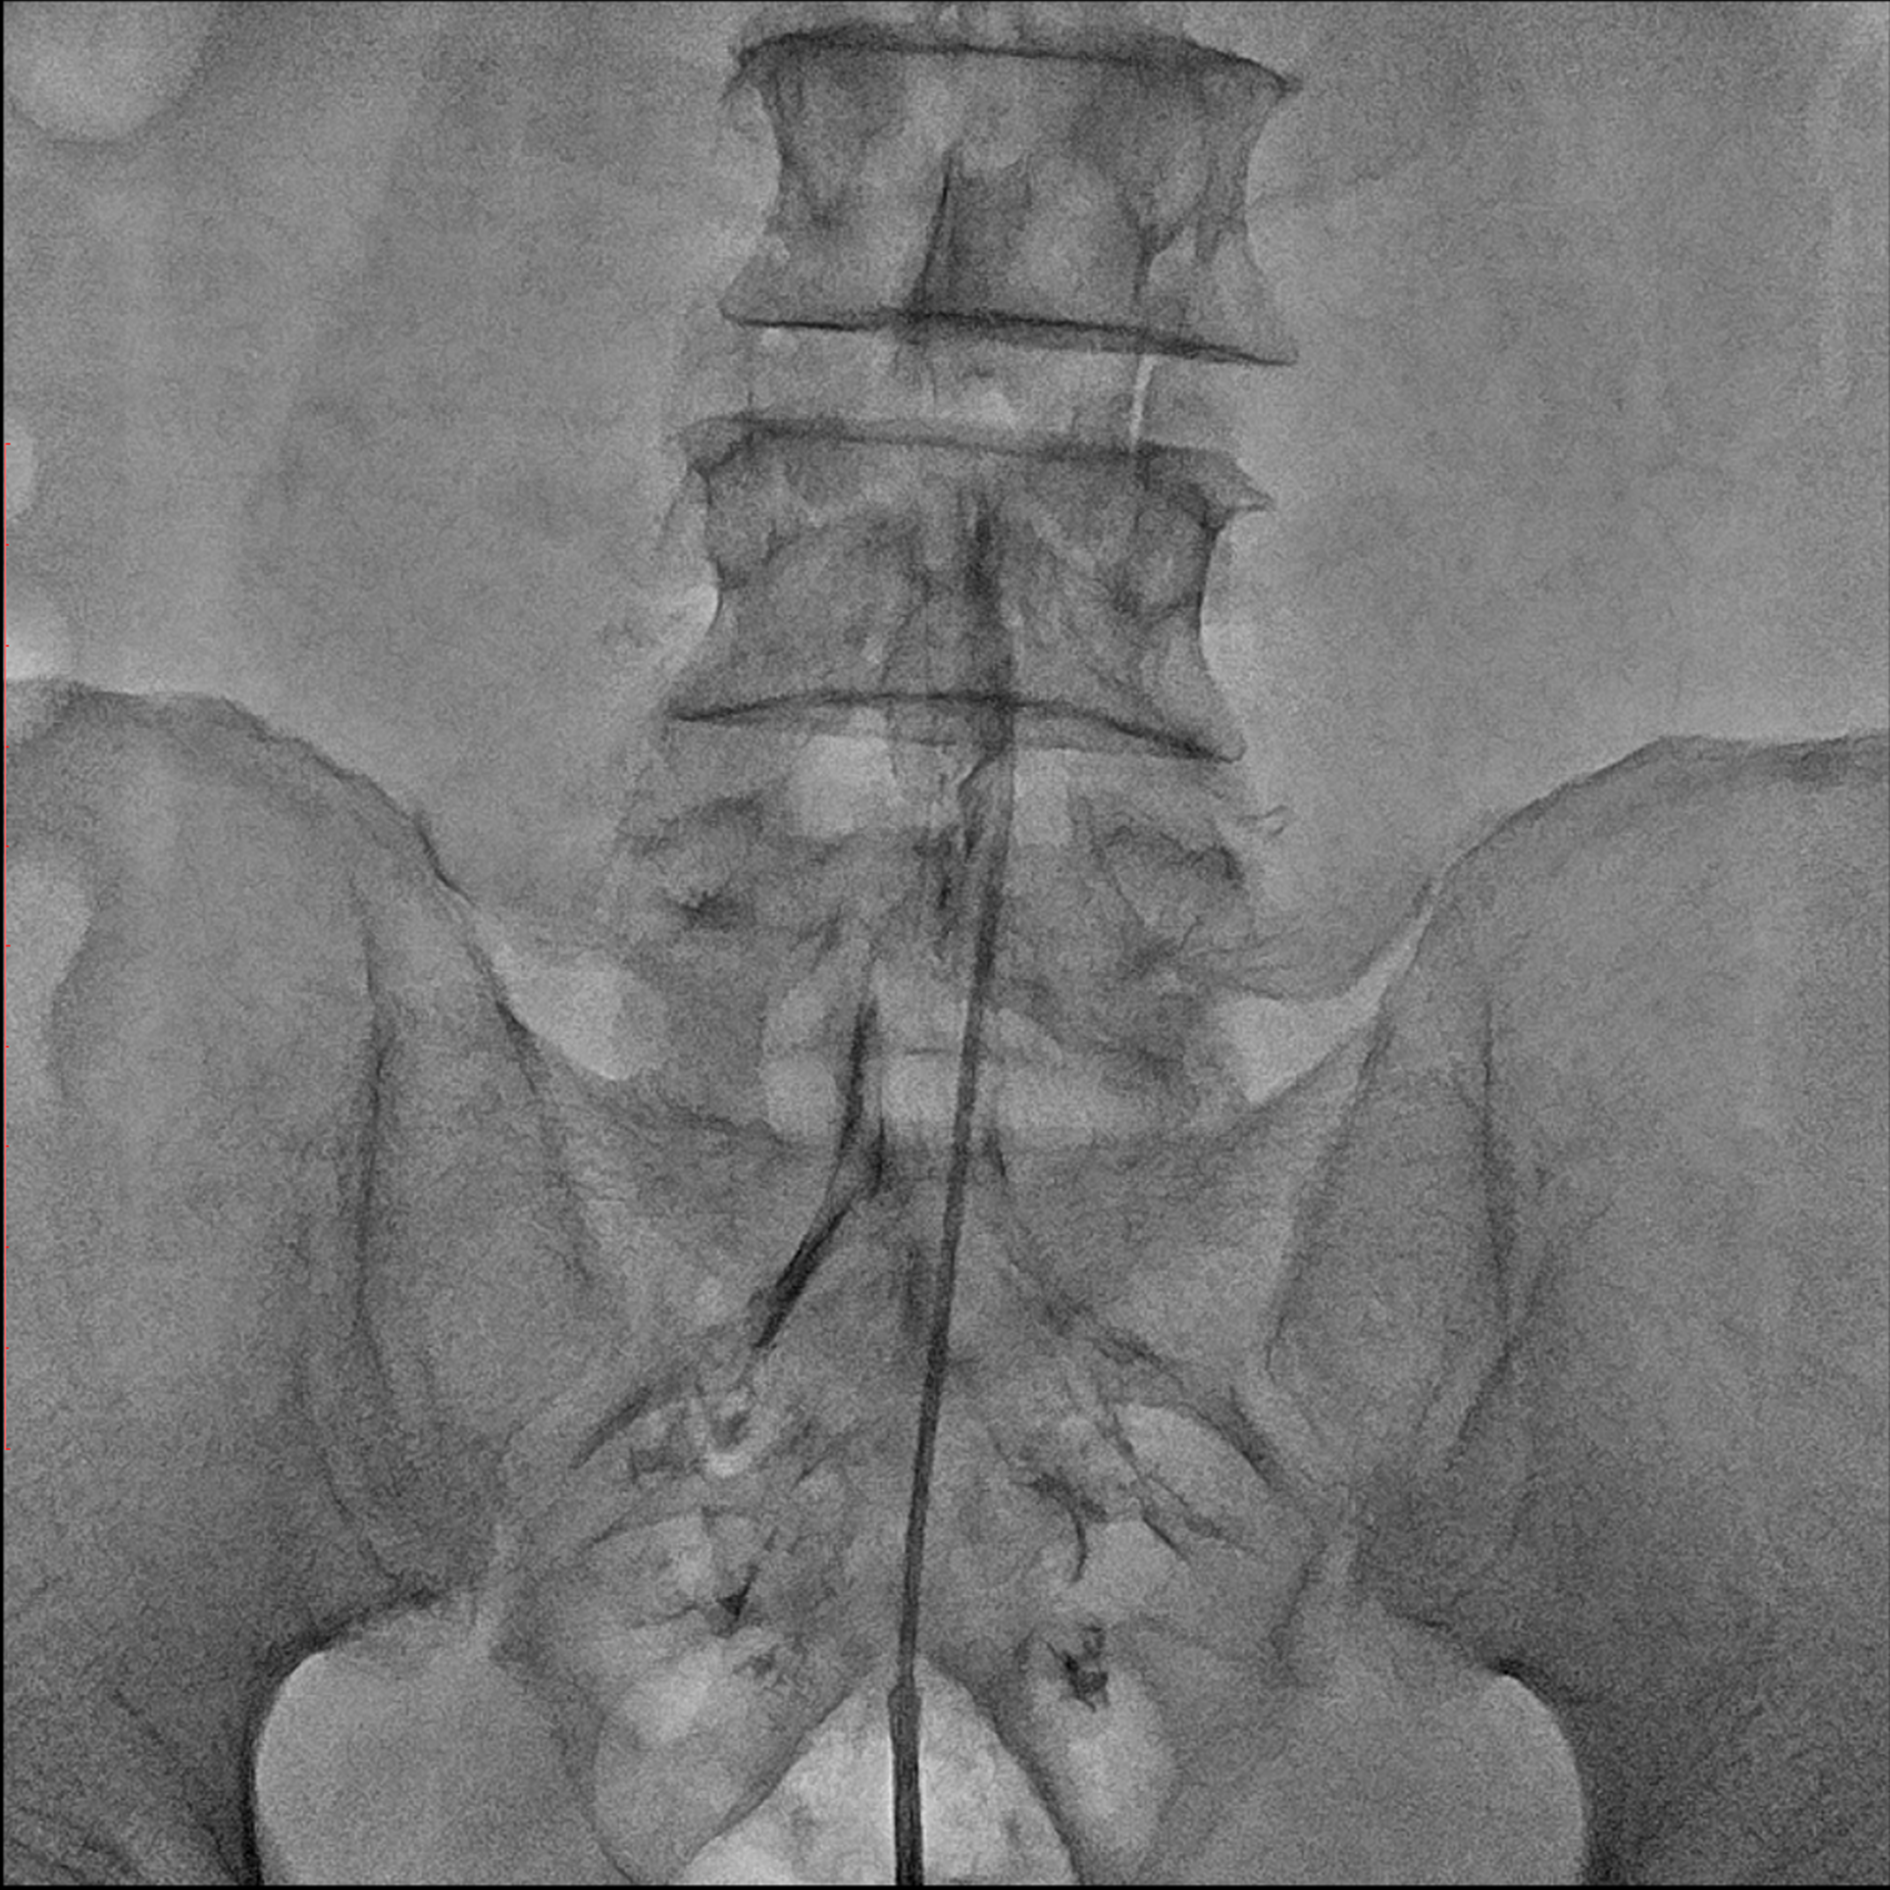

경막외 유착박리술, Epidural Neuroplasty